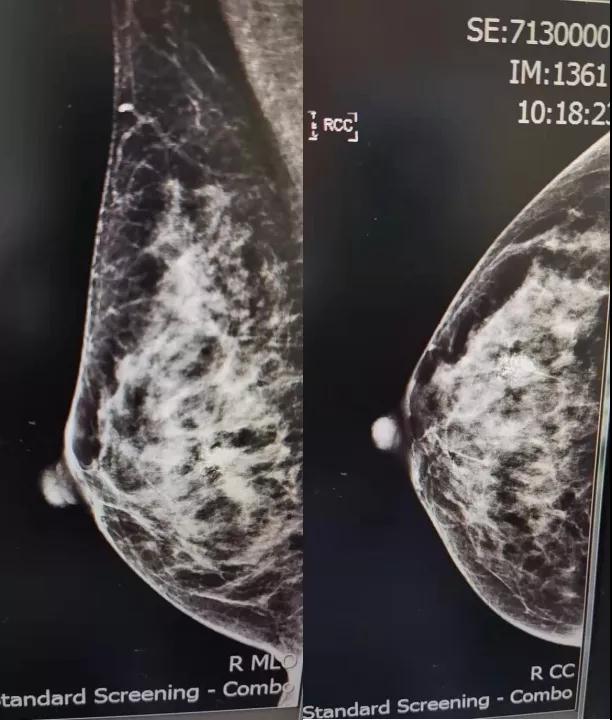

钼靶:右乳成簇钙化考虑恶性 [B1-RADS:4C类]。

术前钼靶